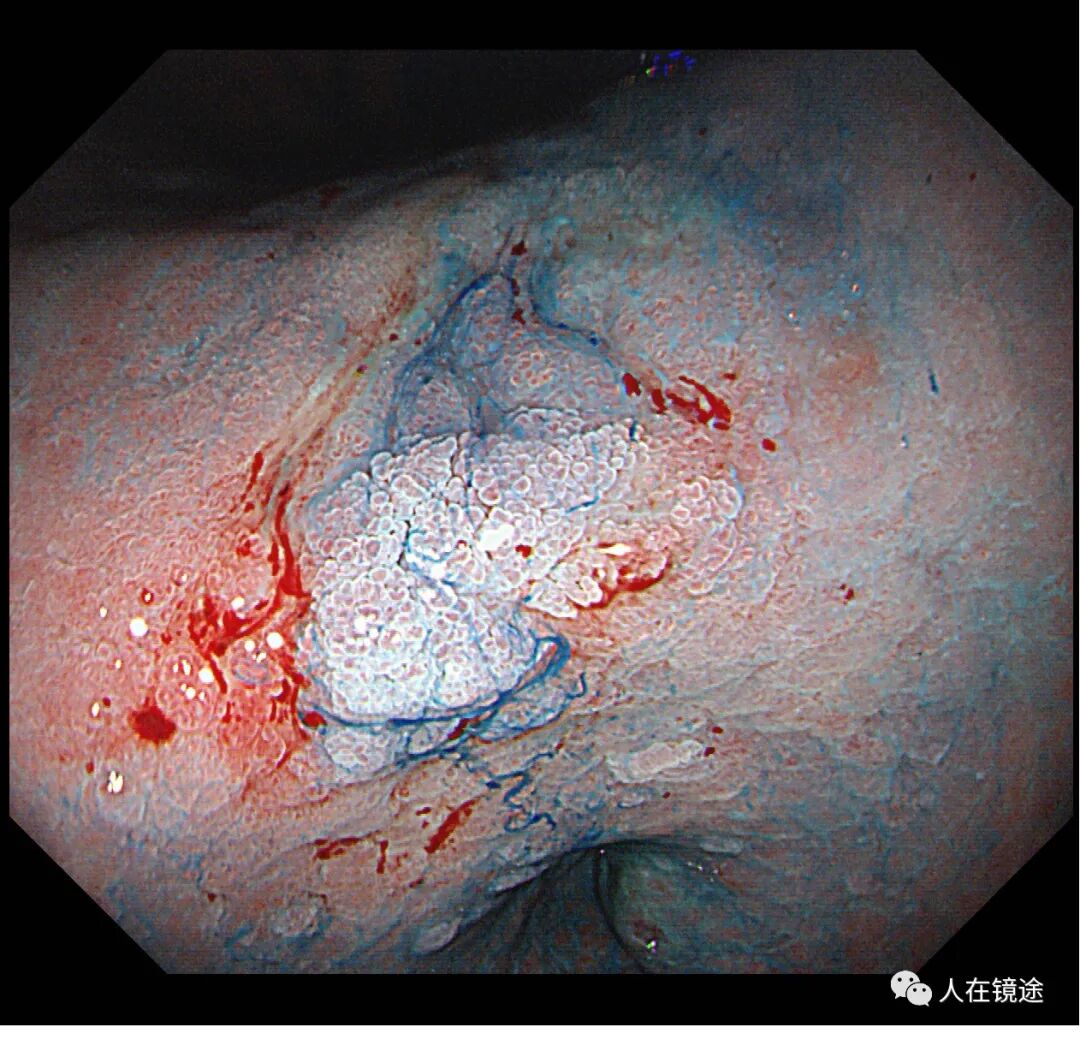

靛胭脂染色示:病变边界清楚,约0.8*1.2cm大小,表面粘膜高低不平,微结构紊乱伴自发性出血。

NBI+靛胭脂+近焦示:病变边界清楚,约0.8*1.2cm大小,表面粘膜高低不平,微结构紊乱伴自发性出血

靛胭脂+醋酸示:病变边界清楚,约0.8*1.2cm大小,表面粘膜高低不平,微结构紊乱伴自发性出血,中央见腺管密集不规则,

NBI+靛胭脂+醋酸+近焦示:病变边界清楚,约0.8*1.2cm大小中央见腺管密集不规则伴自发性出血。